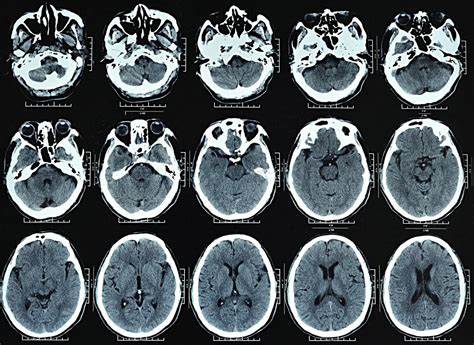

据eurekalert.org网站报道,全球首个可捕捉人体三维图像的医学成像扫描仪“探索者”完成了首次扫描任务。11月24日在美国芝加哥举行的北美放射学会会议上,这台全新的扫描仪将与世人见面。

“探索者”由美国加州大学戴维斯分校的研究人员西蒙·切里和拉姆齐·巴达维与汇影医疗公司等联合开发。“探索者”结合了正电子发射断层扫描仪和X射线计算机断层扫描仪的功能,可以同时对整个人体进行成像,其对辐射的捕捉效率更高,最短成像时间仅为一秒钟。此外,“探索者”还能够对标记药物在全身的运移情况进行跟踪拍摄。将“探索者”投放到医疗保健市场,可对诊断技术、疾病跟踪和新药创制等带来显著改善。加大生物医学工程教授切里感慨道:“虽然多年来我们一直对全身扫描仪的成像效果充满憧憬,但当我真的看到‘探索者’首次扫描提供的惊人细节时,竟让人有点不知所措。尽管‘探索者’还有很多地方有待进一步改进,但它基本达到了我们的预期。”加大核医学主任、放射学研究副主任巴达维同样对“探索者”的成像能力感到震惊。他说:“在获得优化的重建方法后,‘探索者’能提供的细节是其他扫描仪无法媲美的。”

切里预计,“探索者”可对未来的医疗行业产生深远的影响——“探索者”的扫描速度是传统断层扫描仪的40倍,而辐射剂量仅为其40分之一。这对于个案的重复研究和儿科病患的累积辐射量控制非常有意义。此外,“探索者”还首次实现了对人体所有器官状况的同时评估。例如,它可以定量测定血液流动或葡萄糖在人体各处的吸收情况。研究人员可以根据这些数据分析肿瘤的扩散和代谢紊乱等症状。